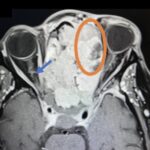

Sinonasal carcinoma is a rare malignancy that often presents with nonspecific symptoms, making early diagnosis challenging. Delayed recognition can lead to disease progression and worse outcomes. This case report emphasizes the importance of early identification, prompt imaging, and multidisciplinary management. A 73-year-old male with a history of anemia and hypertension presented with progressive facial swelling, 20-pound weight loss, and vision loss in the left eye over two months. Initially misdiagnosed with bacterial sinusitis, his symptoms persisted. Examination revealed a proptotic left eye and a large obstructive nasal mass. Computed tomography (CT) and MRI (magnetic resonance imaging) demonstrated a destructive sinonasal mass with skull base and intracranial extension. A biopsy confirmed sinonasal carcinoma, and the patient was started on chemoradiation therapy due to the inoperability of the tumor.

This case underscores the importance of recognizing red flag symptoms such as persistent facial swelling and neurological deficits. Multimodal imaging played a critical role in diagnosis. The literature suggests sinonasal carcinoma is often diagnosed late, reinforcing the need for early suspicion and specialist referral. Sinonasal carcinoma should be considered in patients with persistent facial or nasal symptoms. Timely imaging, biopsy, and interdisciplinary care are essential for optimizing outcomes.